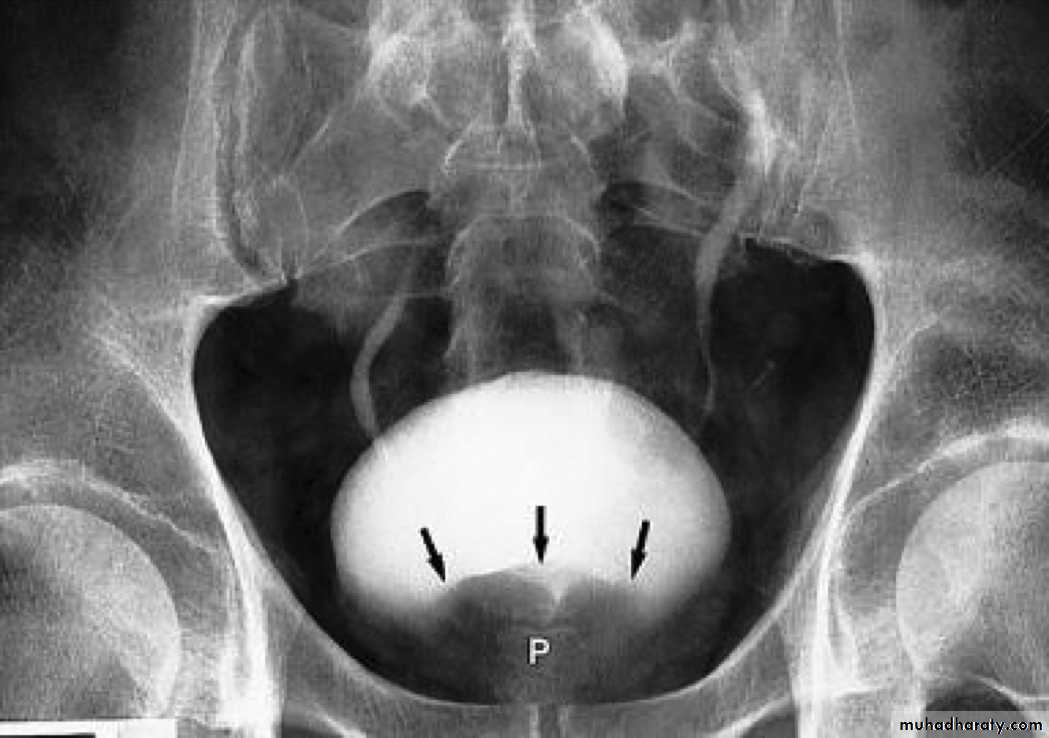

radiographic appearance in bladder exstrophy. It describes wide midline separation of the pubic bones.Bladder exstrophy (also known as ectopia vesicae) refers to a herniation of the urinary bladder through an anterior abdominal wall defect. The severity of these defects is widely variable.

BPH with elevated bladder base